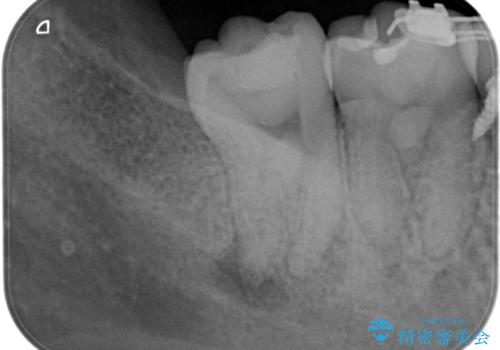

- 奥の歯茎にニキビみたいなものができたことを主訴に来院されました。

来院時は特に痛みはありませんでしたが、5年ほど前は痛みがあり、他院で虫歯の治療をしたことがあるとのことでした。

歯髄検査をし、歯髄壊死と診断できたため治療を介入しています。

咬合面の修復材料を除去すると内部に細菌の塊である多量のカリエスが残存しており、それが原因で歯髄が壊死したと考えられます。

治療中、細菌の除去を徹底的に行えるように顕微鏡とラバーダム(ゴムのシート)を用いて行いました。